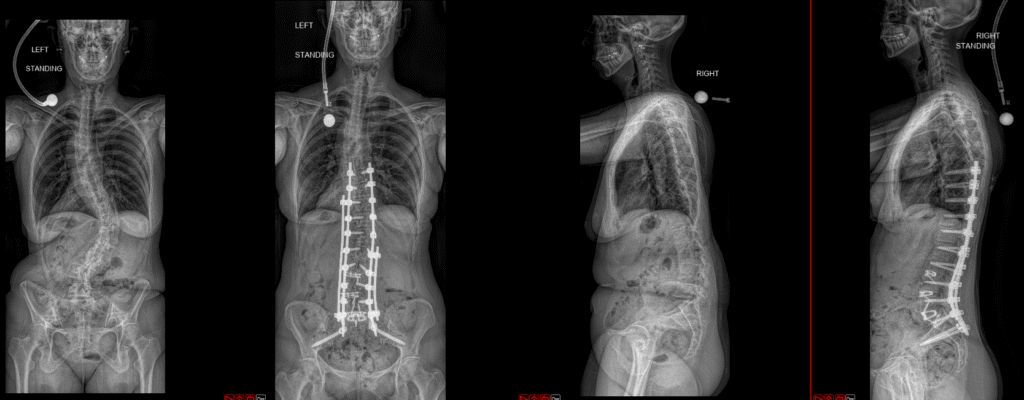

Deformity Surgery